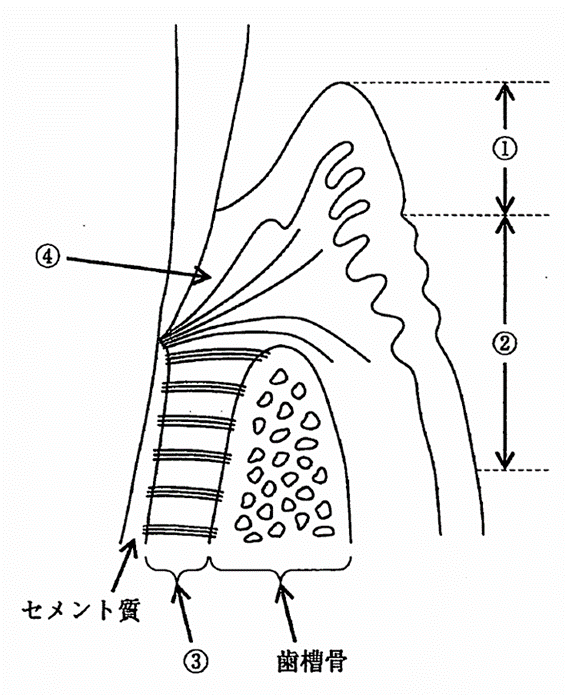

歯周組織の模式図を示す。①~④の説明で正しいのはどれか。2つ選べ。

a. ①は角化上皮で覆われている。

b. ②は可動性の粘膜である。

c. ③はコラーゲン線維に富んでいる。

d. ④は歯と結合組織付着している。

解答を見る

a.c